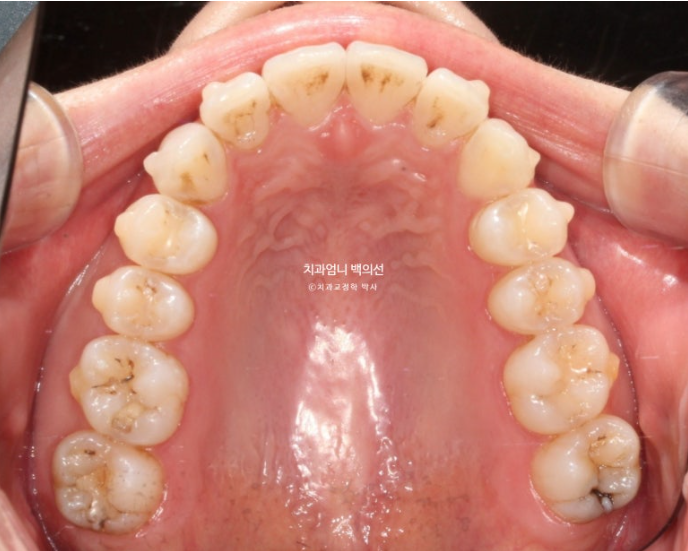

위 아래 치아중심선이 어긋나 있고 아래 앞니 하나가 솟으면서 뒤로 들어가 있습니다.

어금니 교합은 좋죠.

이런 경우는 인비절라인의 프로그램 중 인비절라인 라이트로 교정하면 기간 비용대비 환자분의 만족도가 가장 좋습니다.